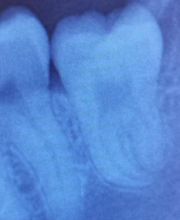

Seestrasse 160, 8806 BächZahnarzt · Zahnersatz · Kieferorthopädie · Implantologie

Seit 1995 dürfen wir Sie in Bäch an der Seestrasse willkommen heissen. Ihre orale und dentale Gesundheit ist und bleibt unser Hauptziel. Wir beraten Sie gerne auf dem Weg dorthin. Vereinbaren Sie noch heute einen Termin beim Zahnarzt oder der Dentalhygienikerin.